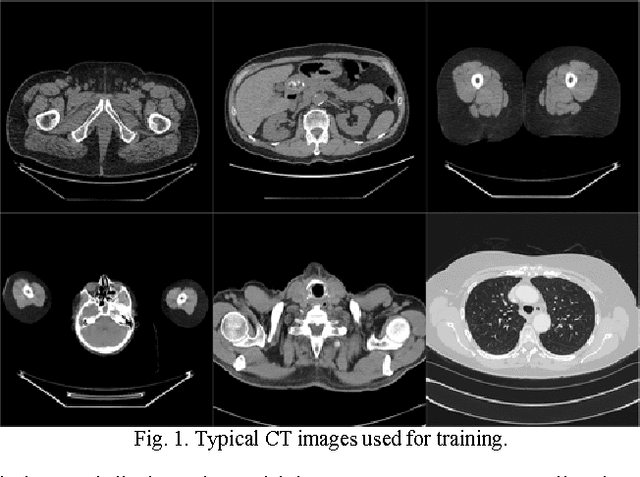

To reduce the potential radiation risk, low-dose CT has attracted much attention. However, simply lowering the radiation dose will lead to significant deterioration of the image quality. In this paper, we propose a noise reduction method for low-dose CT via deep neural network without accessing original projection data. A deep convolutional neural network is trained to transform low-dose CT images towards normal-dose CT images, patch by patch. Visual and quantitative evaluation demonstrates a competing performance of the proposed method.